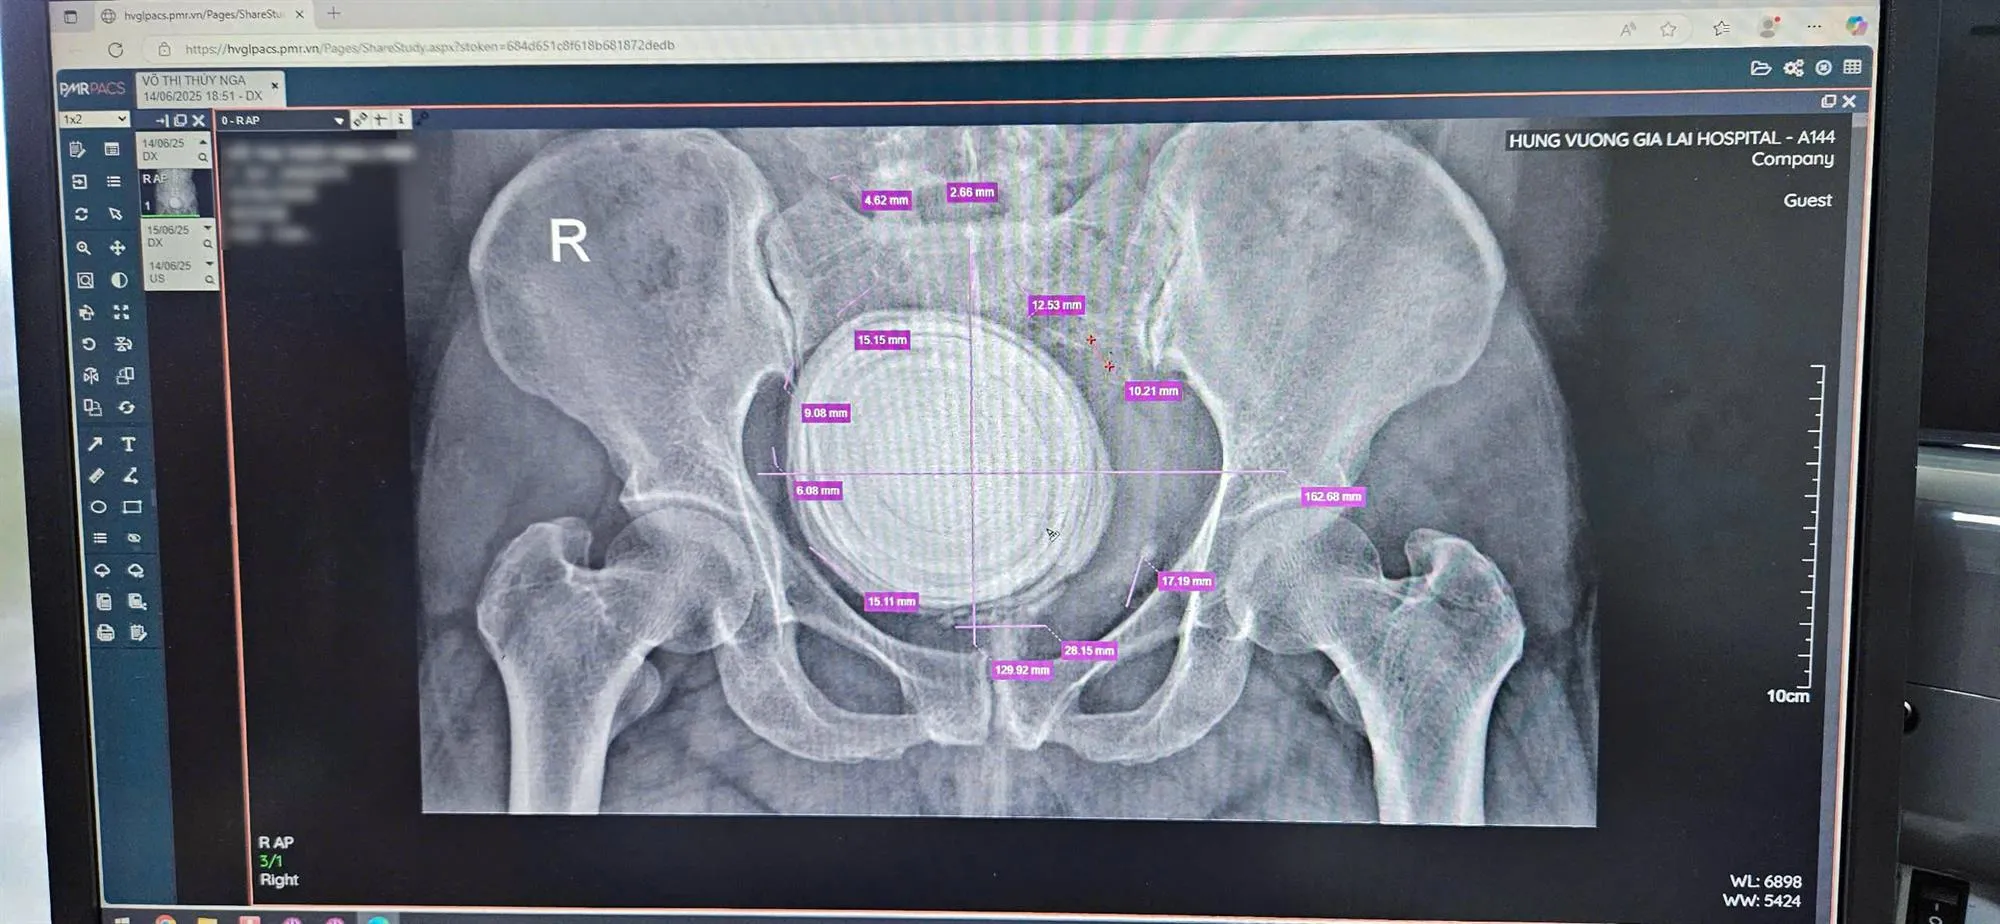

Bệnh nhân nhập viện trong tình trạng tiểu buốt, tiểu ra cặn sỏi, đau tức vùng hạ vị. Qua thăm khám, các bác sĩ phát hiện tiền sử sỏi bàng quang từ nhỏ. Viên sỏi kích thước hơn 10 cm chiếm toàn bộ lòng bàng quang, gây nguy cơ tổn thương niêm mạc và suy giảm chức năng tiểu tiện.

Do kích thước sỏi quá lớn, không thể tự tống xuất, các bác sĩ quyết định phẫu thuật mở bàng quang. Ca mổ diễn ra thuận lợi, viên sỏi được lấy ra an toàn. Hiện sức khỏe bệnh nhân V.T.T.N ổn định, vết mổ tiến triển tốt.

Hình ảnh viên sỏi đường kính 10cm và vỏ bọc dập nát cho thấy mức độ nghiêm trọng của tình trạng. Bệnh nhân chia sẻ cảm giác "nhẹ nhõm" sau nhiều năm chịu đựng cơn đau dai dẳng, đánh dấu bước ngoặt trong hành trình điều trị.

Thạc sĩ, bác sĩ nội trú Hoàng Văn Công, Khoa Ngoại Tổng hợp, cho biết trường hợp của bệnh nhân V.T.T.N rất đặc biệt. Sống chung với sỏi bàng quang gần 30 năm, bệnh nhân âm thầm chịu đựng mà không điều trị sớm.